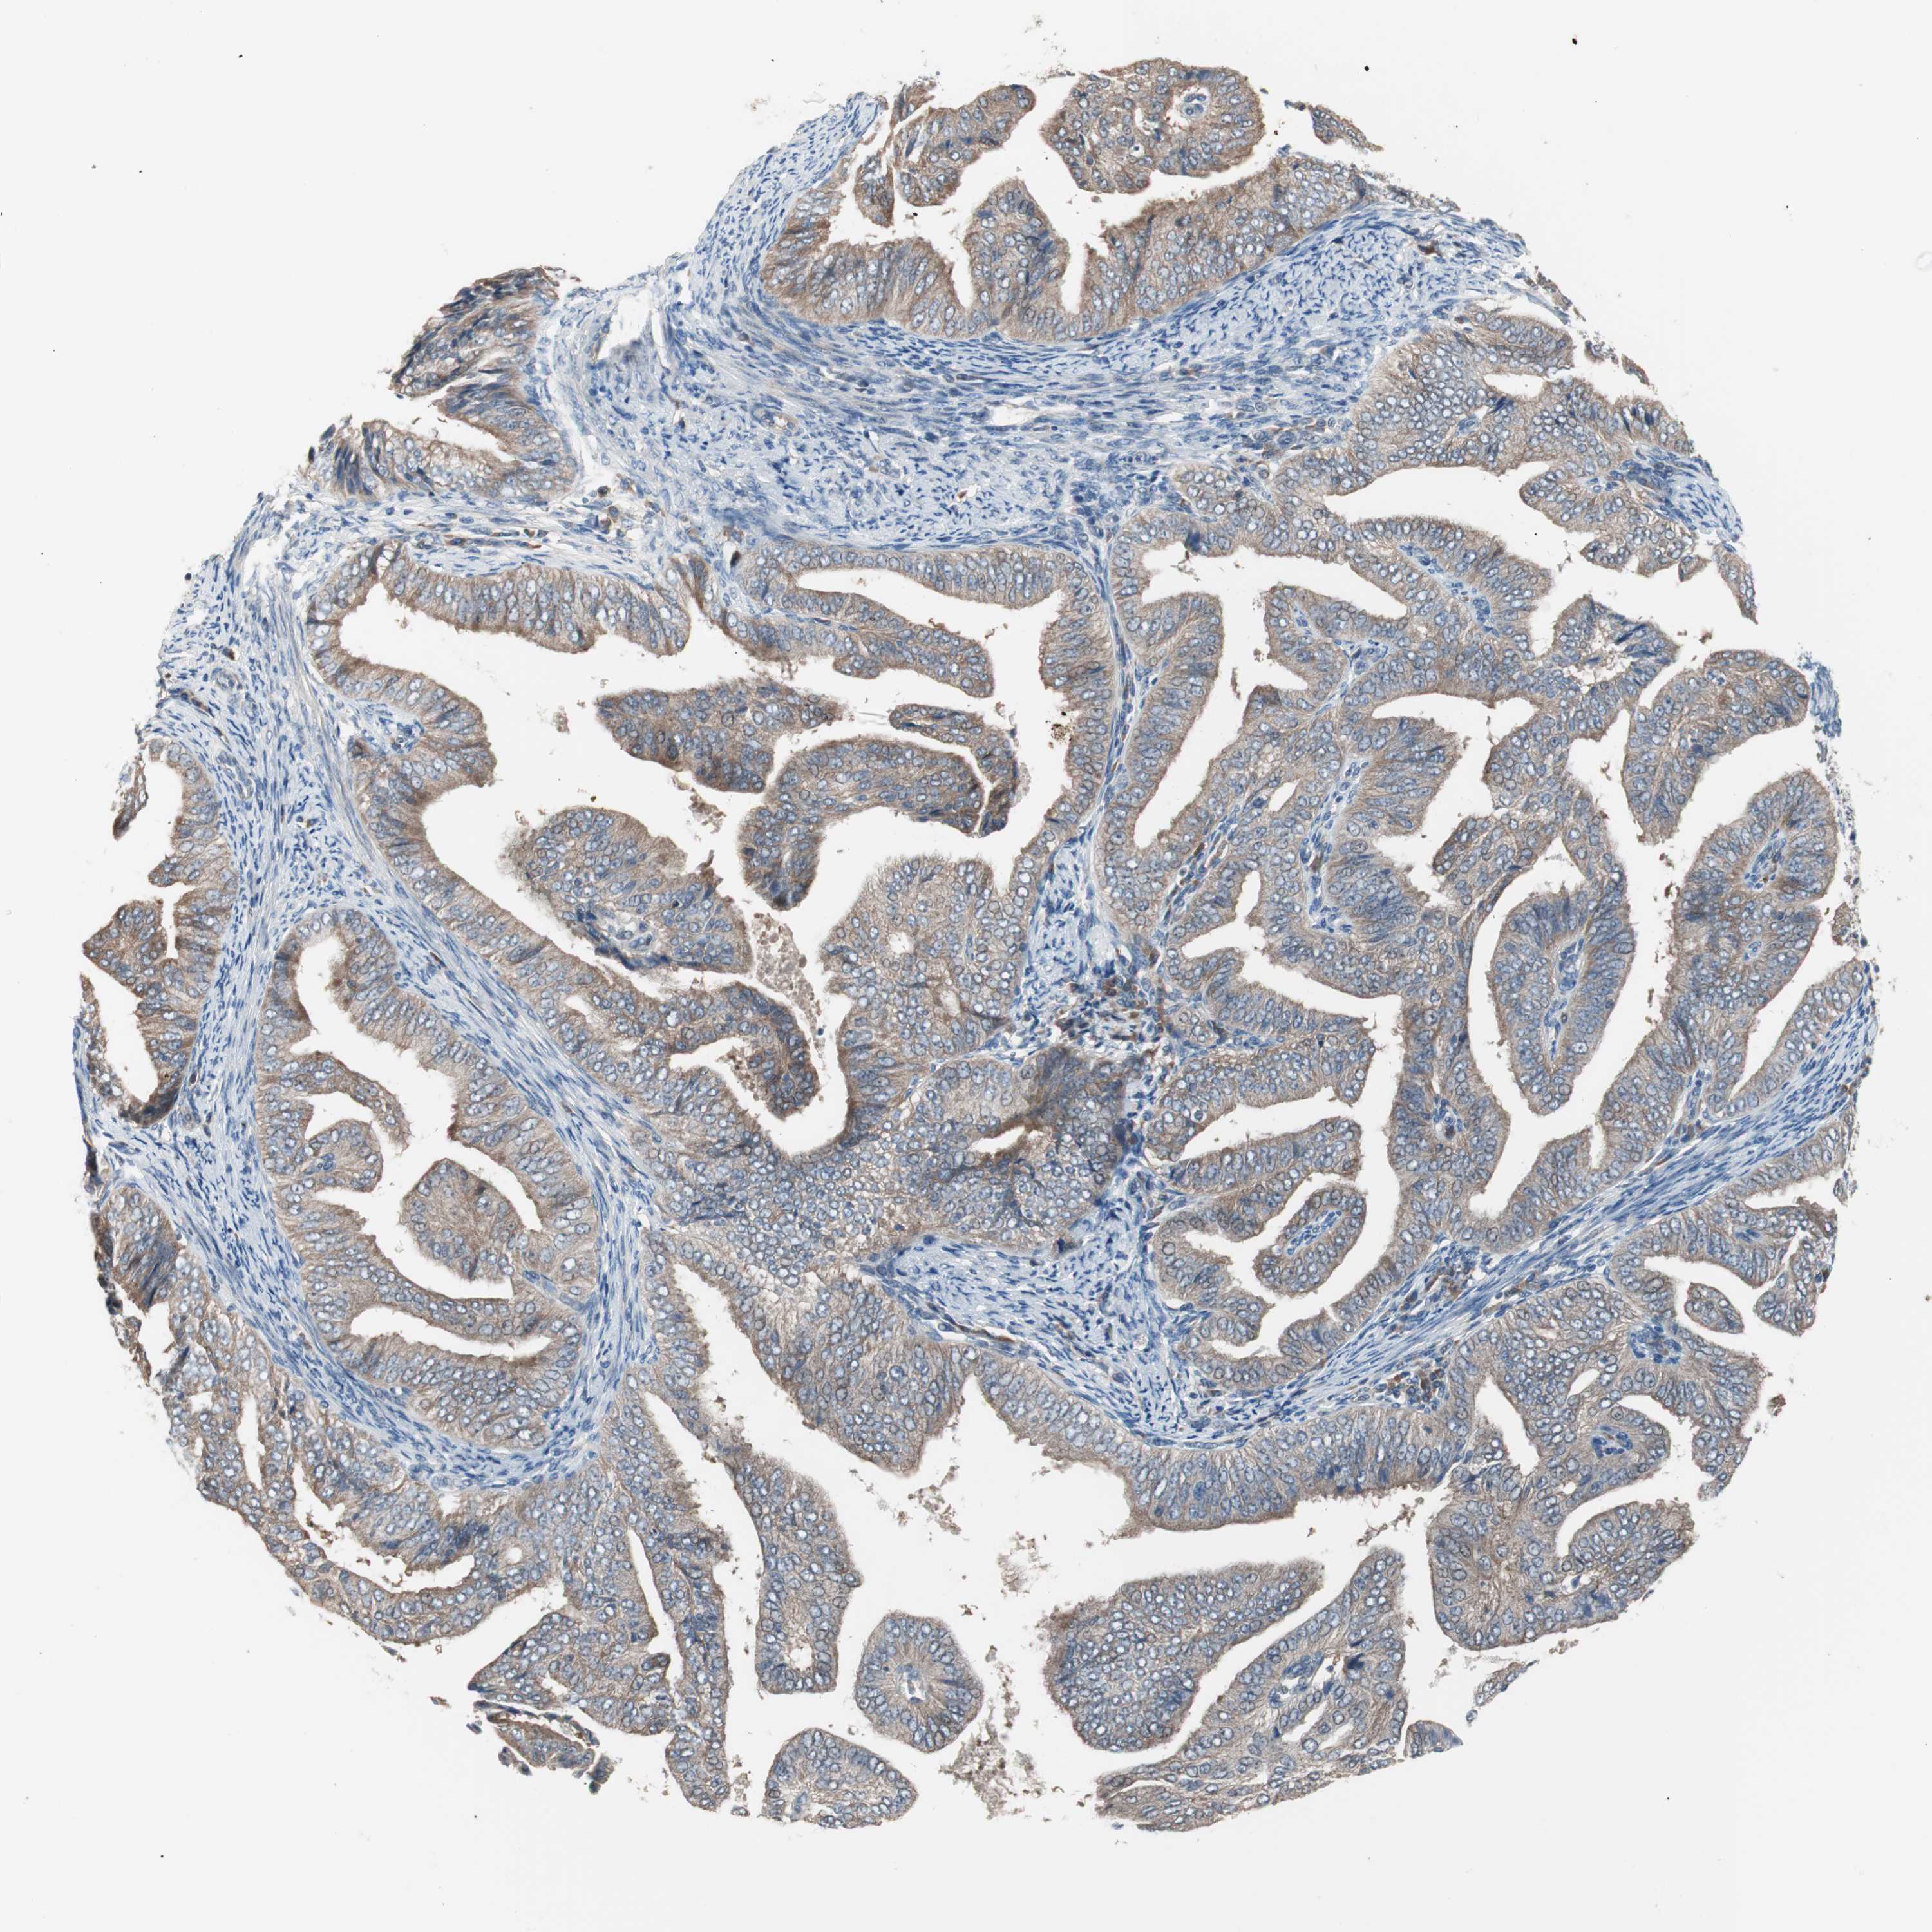

ENDOMETRIAL CANCER - Protein expressioni

A mouse-over function shows sample information and annotation data. Click on an image to view it in a full screen mode. Samples can be filtered based on level of antibody staining by selecting one or several of the following categories: high, medium, low and not detected. The assay and annotation is described here.

Note that samples used for immunohistochemistry by the Human Protein Atlas do not correspond to samples in the TCGA dataset.

Antibody stainingi

Antibody staining in the annotated cell types in the current human tissue is reported as not detected, low, medium, or high, based on conventional immunohistochemistry profiling in selected tissues. This score is based on the combination of the staining intensity and fraction of stained cells.

Each image is clickable and will lead to virtual microscopy that enables deeper exploration of all samples and also displays staining intensity scores, fraction scores and subcellular localization as well as patient and tissue information for each sample.

Antibody HPA006277

Antibody HPA006507

Antibody CAB017027

Staining

High

Medium

Low

Not detected

Intensity

Strong

Moderate

Weak

Negative

Quantity

>75%

75%-25%

<25%

None

Location

Nuclear

Cytoplasmic/membranous

Cytoplasmic/membranous,nuclear

Adenocarcinoma, NOS